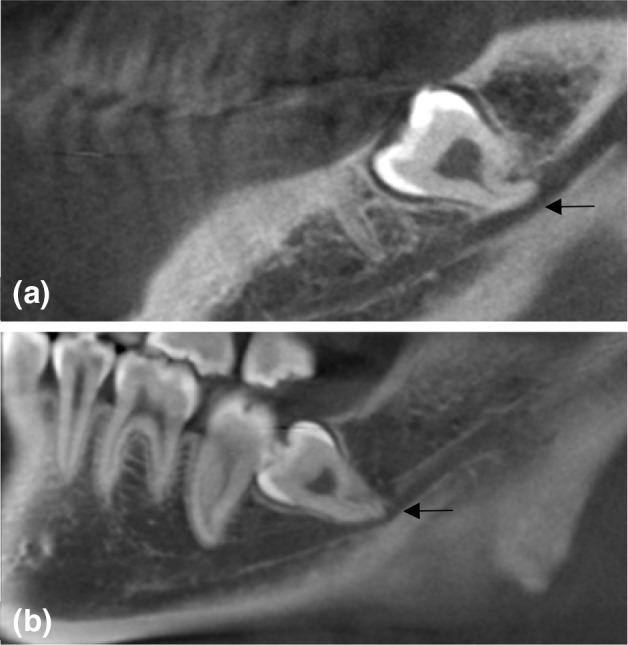

The positional relationship between the mandibular canal and corresponding third molars is a key anatomic factor of inferior alveolar nerve (IAN) injury. The aim of the present study is to classify the anatomic three-dimensional relationship between the mandibular third molar and the mandibular canal on cone-beam computed tomography (CBCT) images.

This study used CBCT images to classify the positional relationship between the mandibular canal and corresponding third molars. CBCT images of 749 patients (1296 mandibular third molars) were analyzed to draw up a classification.

On a total of 1296 third molars, the mandibular canal relative to the roots of the mandibular third molar was on the apical side (88.1%), followed by the buccal side (7.9%), the lingual side (3.5%), and then between the roots (0.5%). Ninety-five (7.1%) third molars had a close relation with the mandibular canal, while 1201 (92.7%) third molars had no direct contact. The percentage of the mandibular canal contacts with the mandibular third molar was higher when the mandibular canal was lingually positioned.